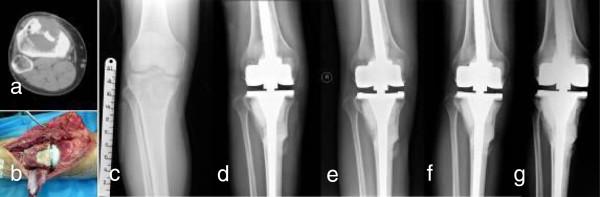

Giant cell tumors (GCT) around the knee are common and pose a special problem of reconstruction after tumor excision, especially for grade III GCT. We questioned whether en bloc resection and reconstruction with alcohol inactivated autograft-prosthesis composite would provide (1) local control and long-term survival and (2) useful limb function in patients who had grade III GCT around the knee.

We retrospectively reviewed eight patients (5 males and 3 females) treated with this procedure with mean age of 31 years (range 20 to 43 years) from Jan 2007 to Oct 2008. 5 lesions were located in distal femur and 3 in proximal tibia. 4 patients were with primary tumor and the other 4 with recurrence. 2 patients showed pathological fracture.

Mean Follow-up is 54 months ranging from 38 to 47 months. No recurrence, metastasis, prosthesis loosening were found. The mean healing time between autograft and host bone was 5.5 months. The mean MSTS score was 26.3 (88%) ranging from 25 to 29. The mean ISOLS composite graft score was 32.8 (88.5%) ranging from 28 to 35. Creeping substitution is possibly the main way in bony junction. The healing time in femoral lesion is faster than that in tibial lesion.

The technique of alcohol inactivated autograft-prosthesis composite could be able to achieve satisfactory oncological and functional outcomes in Grade III GCT.